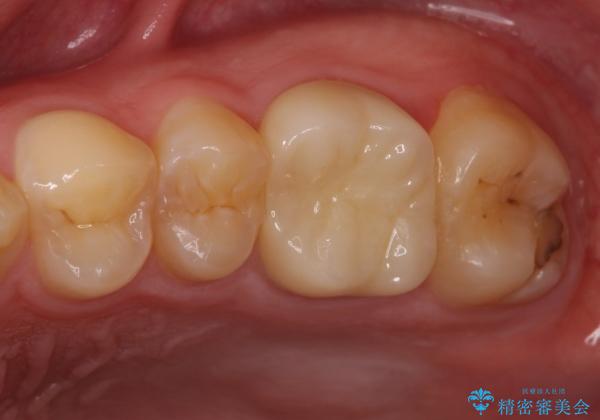

根管治療中の転院 奥歯のオールセラミック治療

- ラバーダムや顕微鏡を用いた根管治療を希望されて、転院された患者様です。

前医にて神経を取り除いた処置を行った際、ラバーダムが使用されなかったとのことで転院されてきました。

根管治療を実施した後、フルジルコニアクラウンに補綴することとしました。

前医での処置後、治療前には気にならなかった痛み続いていたようですが、当院での処置後は痛みが徐々に引いていき、治療から半年が経過した時点では全く違和感も感じなくなりました。

根管治療後のクラウンも、まるでもとの自分の歯のように自然な仕上がりとなり、患者様には大変満足していただけました。